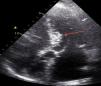

Case reportWe describe the case of a 73-year-old woman with acromegaly due to a pituitary adenoma diagnosed and treated surgically at the age of 38 but with recurrence and reoperation at the age of 50. She had a history of hypertension, multinodular goiter and atrial fibrillation under oral anticoagulation. She was referred to our cardiology department due to echocardiographic evidence of obstructive hypertrophic cardiomyopathy and a three-month history of progressively worsening exercise-induced dyspnea and orthopnea (NYHA class III) under optimal medical therapy. A complete echocardiogram revealed severe asymmetric hypertrophy of the left ventricle, mostly in the basal portion of the interventricular septum (19 mm), without LV dilation, depressed ejection fraction or wall motion abnormalities. There was also a dynamic LVOT obstruction gradient of 70 mmHg at rest and of 120 mmHg with Valsalva maneuver and systolic anterior movement (SAM) of the mitral valve with mild regurgitation and moderate to severe tricuspid regurgitation. A better characterization with magnetic resonance imaging confirmed basal interventricular septal hypertrophy without evidence of intramyocardial fibrosis (Figure 1). Genetic testing excluded the most frequent forms of familial hypertrophic cardiomyopathy. A 24-hour Holter examination revealed permanent atrial fibrillation but no ventricular repolarization or heart rate abnormalities. After a multidisciplinary discussion, ASA was performed, guided by myocardial contrast echocardiography, with injection of 2 cc of alcohol in the first septal branch of the left coronary artery (Figures 2–4). The procedure was uneventful and no atrioventricular (AV) conduction disturbances were detected. The one-year echocardiographic reassessment showed a reduction of the interventricular septum to 13 mm and of 8 mm in the region treated by ASA. The LVOT gradient was 28 mmHg at rest and the SAM of the mitral valve and the moderate to severe tricuspid regurgitation had disappeared. The patient improved significantly to mild-to-moderate heart failure (NYHA class I-II) and no major cardiovascular events were observed during follow-up.